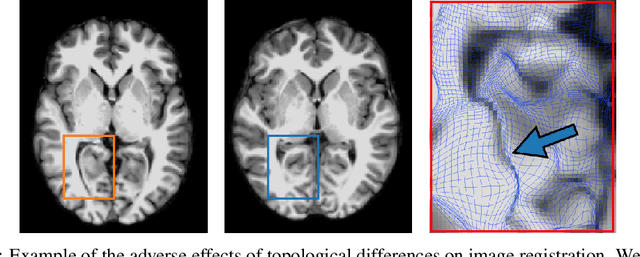

Geometric alignment appears in a variety of applications, ranging from domain adaptation, optimal transport, and normalizing flows in machine learning; optical flow and learned augmentation in computer vision and deformable registration within biomedical imaging. A recurring challenge is the alignment of domains whose topology is not the same; a problem that is routinely ignored, potentially introducing bias in downstream analysis. As a first step towards solving such alignment problems, we propose an unsupervised topological difference detection algorithm. The model is based on a conditional variational auto-encoder and detects topological anomalies with regards to a reference alongside the registration step. We consider both a) topological changes in the image under spatial variation and b) unexpected transformations. Our approach is validated on a proxy task of unsupervised anomaly detection in images.